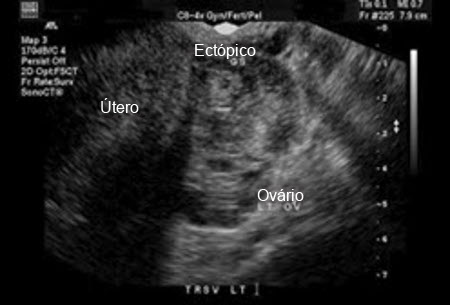

Gravidez ectópica: imagem de ultrassonografia de gravidez ectópica

Do acervo pessoal de Dra. Melissa Fries, Washington Hospital Center; usado com permissão